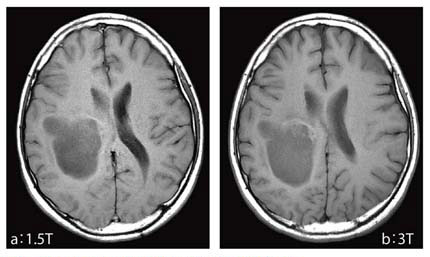

専用 脳MRI 3 高性能MRI(1.5テスラ)|施設・設備|おおたけ脳神経・漢方内科の詳細情報

高性能MRI(1.5テスラ)|施設・設備|おおたけ脳神経・漢方内科。今回導入された3T-MRIについて|名古屋セントラル病院。1.5T MAGNETOM ESSENZA 頭頸部領域における質の高い診断と検査。